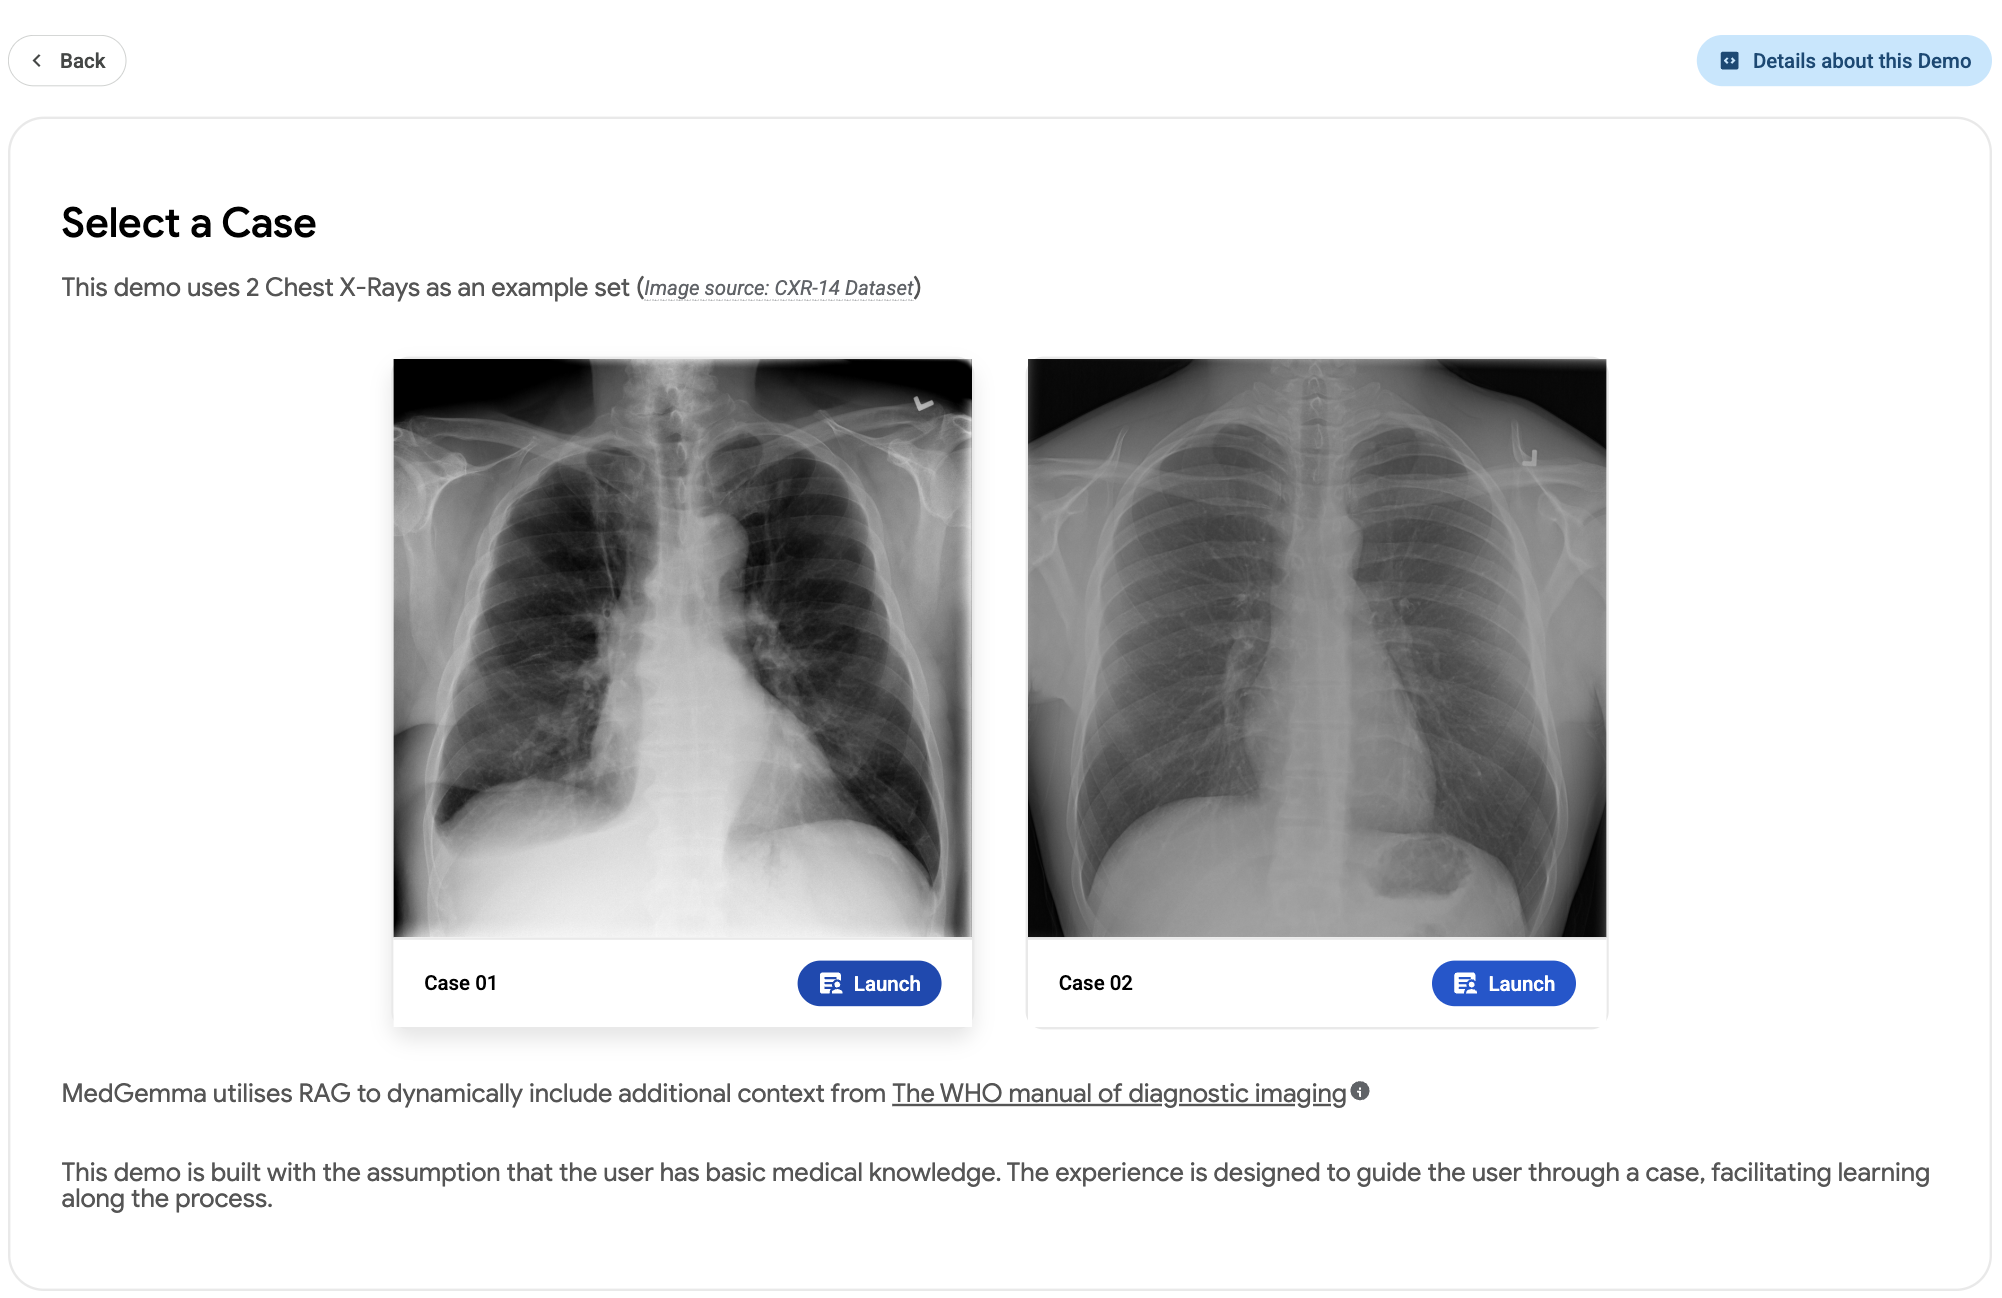

Radiology Image & Report Explainer Demo. Built with MedGemma

A demo showcasing a medical learning experience of CXR image